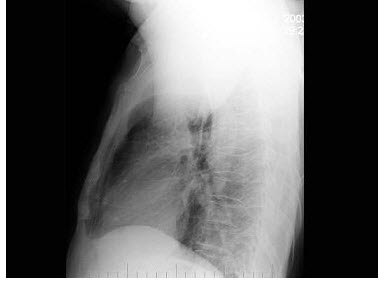

68、单项选择题

女,45岁,寒战、高热1周,WBC:1.8×109/L,胸片如图,应首先考虑()

A.肺结核

B.肺癌

C.肺脓肿

D.肺隔离症

E.大叶性肺炎